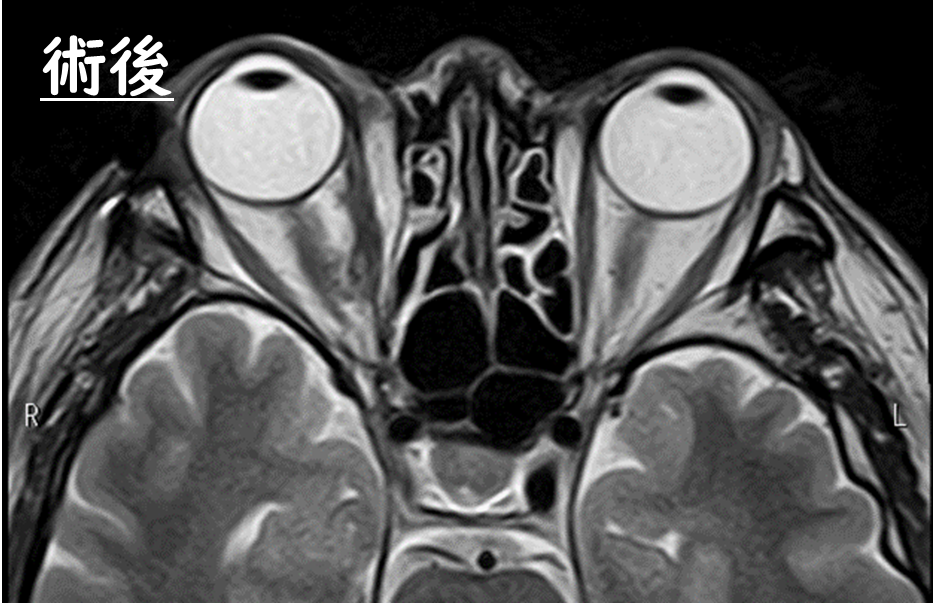

術前のMRI

眼球下方に出現した眼窩腫瘍により眼球が持ち上げられています。